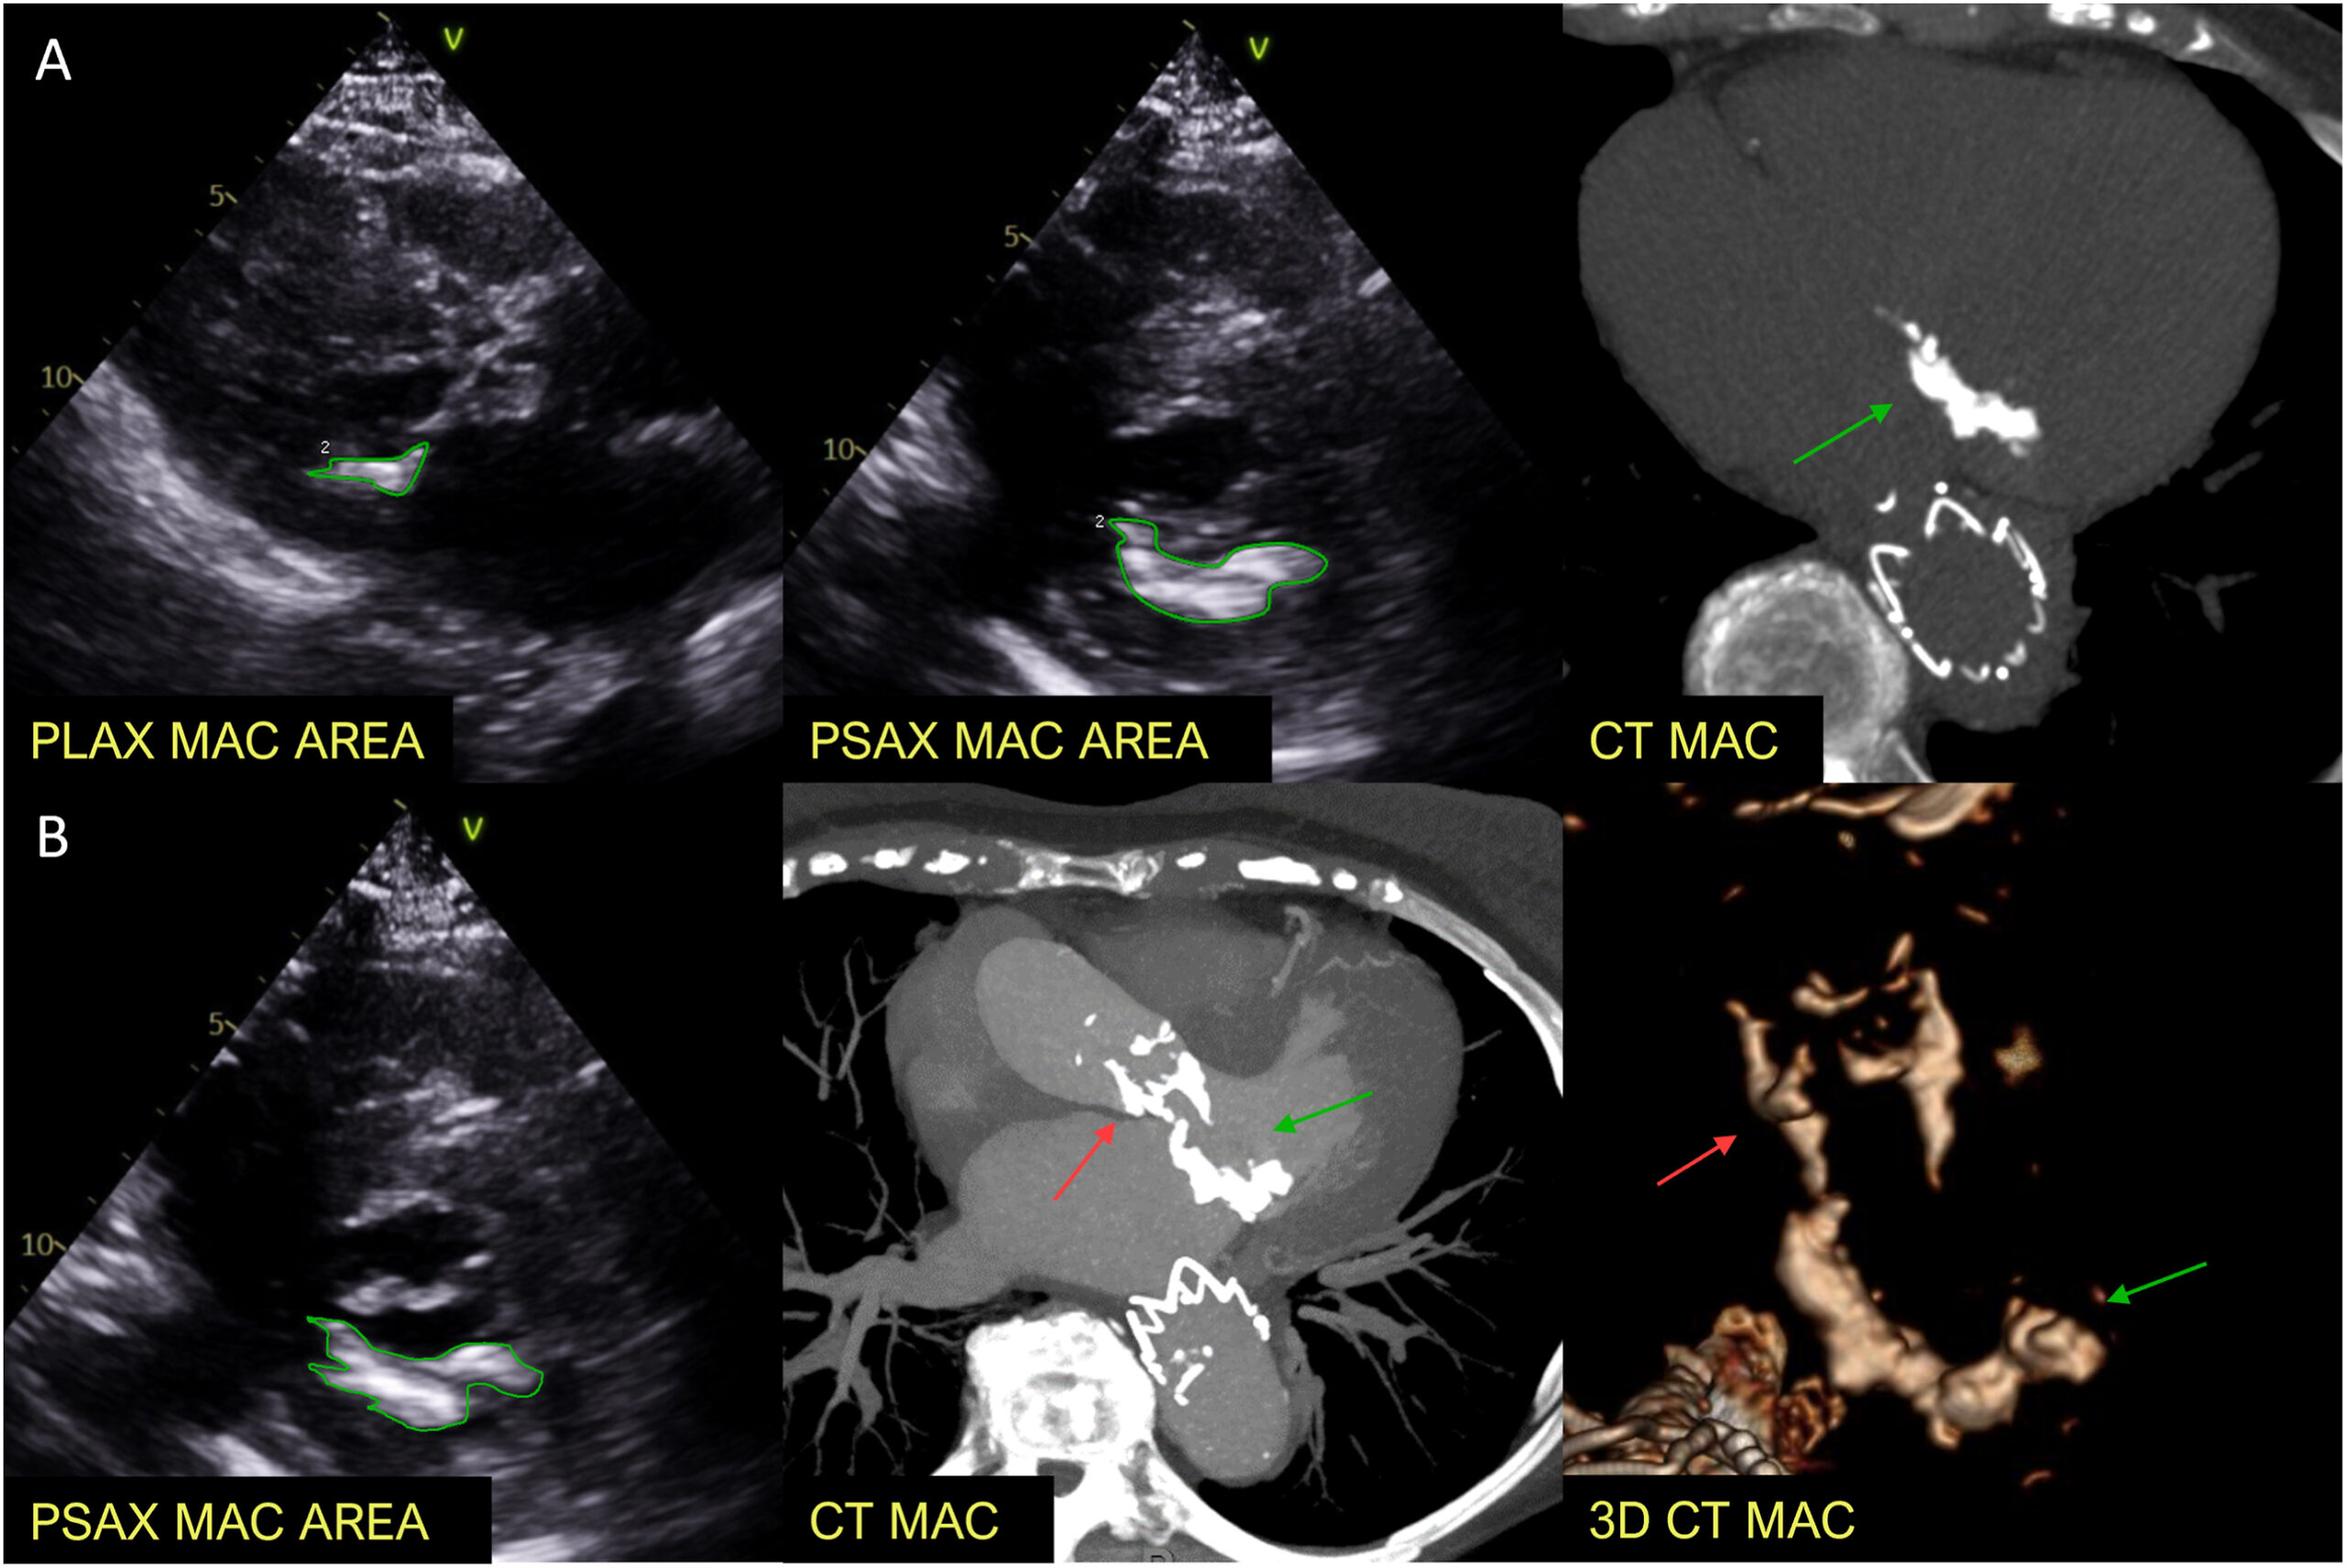

Na recentemente publicada diretriz de avaliação da função diastólica da ASE 2025, um ponto que recebeu destaque foi a calcificação …

Leia maisQuantificação da Calcificação do Anel Mitral: comparação com a tomografia computadorizada